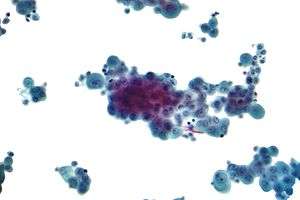

- If cancer is suspected, the pleural fluid is sent for cytology. If cytology is negative, and cancer is still suspected, either a thoracoscopy, or needle biopsy[3] of the pleura may be performed.

Micrograph of a pleural fluid cytopathology specimen showing malignant mesothelioma, one cause of a pleural effusion.